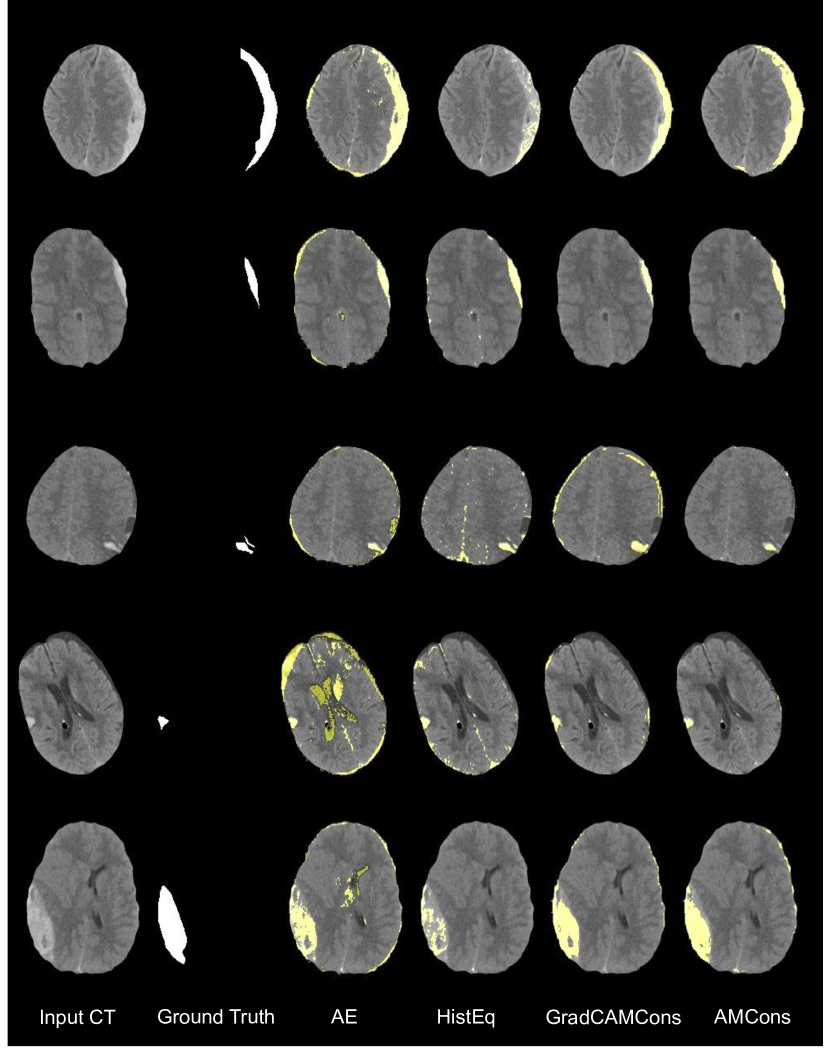

5.3 Generalization to other datasets

In order to empirically demonstrate the generalization properties of the proposed methodology, we evaluate its performance on a different dataset for brain lesion detection. Concretely, as previously described, we resort to Physionet-ICH dataset for non-contrast CT on ICH localization. Implementation details are analogous as the ones used on the BraTS dataset, although we decreased the learning rate to , and we set a larger latent dimension, i.e. , along all baselines and methods to favour model convergence. Obtained results for anomaly localization are reported in Table 4. Even though there exist slight differences in the comparison between residual methods in the literature compared to the results obtained on BraTS dataset (i.e. the simple AE outperforms variations approaches), the proposed attention-based anomaly localization methods still achieve remarkable results. Again, the AMCons configuration yields the best performance, and it reaches improvements of nearly 25% and 18% in terms of AUPRC and DICE, respectively, compared to previous literature. The observed results suggest that the proposed methodology is able to generalize to other unsupervised brain lesion segmentation challenges, even using different imaging modalities. It should be noted, however, that the absolute results in terms of segmentation are lower than those obtained in BraTS. Among other reasons, this may be due to the greater heterogeneity observed in the ICH dataset, the lower degree of standardization and size of the database used, and the small size of ICH lesions, which penalizes metrics such as DICE. Nevertheless, the values obtained are in line with the scarce previous literature on ICH segmentation, as reflected in Table 4. Indeed, the obtained results are at par with previous works using a fully supervised learning approach [22], which shows the difficulty of the task.

5 Additional qualitative visualizations